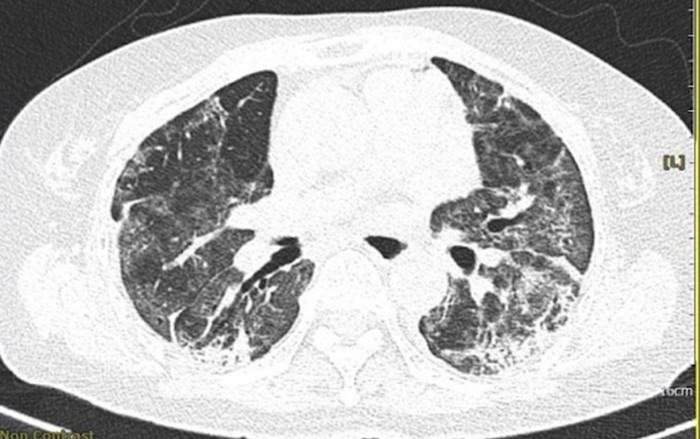

Hình ảnh chụp X-quang phổi của bà Tâm với nhiều đốm trắng xóa, cho thấy mức độ xơ phổi nặng. Ảnh: Bác sĩ cung cấp

Một tháng sau, bà Tâm đến Bệnh viện khám, kết quả chụp X-quang cho thấy xơ phổi hậu Covid, tổn thương xơ phổi nặng hai bên. Tình trạng tổn thương dạng mô kẽ rải rác hai phổi, xơ rải rác, dãi phế quản rải rác hai phổi. Bà phải điều trị dài ngày, đến nay vẫn chưa khỏi.

Di chứng Covid-19 tác động đến phổi ở nhiều mức độ, như tổn thương xơ phổi mức độ nhẹ. Nặng hơn là phổi xơ nhiều (viêm phổi tổ chức hóa), khi ấy hình chụp X-quang phần trắng nhiều hơn đen, bệnh nhân khó thở liên tục, chỉ số oxy trong máu (SpO2) thấp, phải thở oxy tại nhà. Một số bệnh nhân bị nhiễm vô mô phổi lủng lỗ như lao (do lúc cấp tính mắc Covid-19 nặng quá), xơ xẹp phổi.